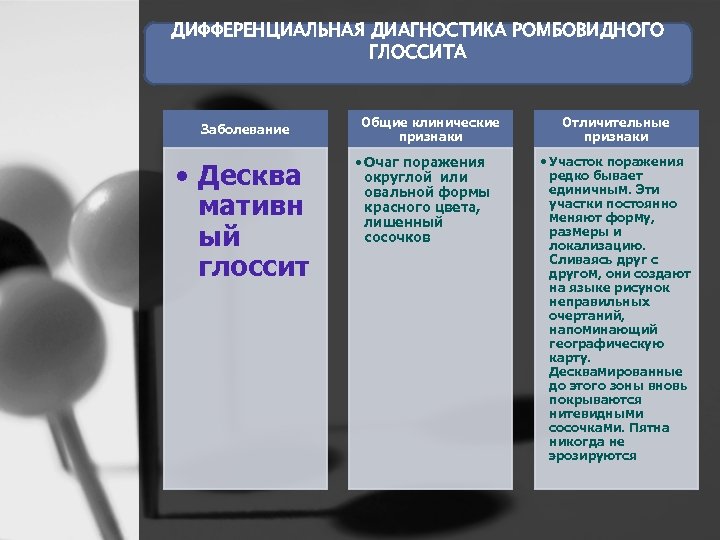

ДИФФЕРЕНЦИАЛЬНАЯ ДИАГНОСТИКА РОМБОВИДНОГО ГЛОССИТА Заболевание • Десква мативн ый глоссит Общие клинические признаки • Очаг поражения округлой или овальной формы красного цвета, лишенный сосочков Отличительные признаки • Участок поражения редко бывает единичным. Эти участки постоянно меняют форму, размеры и локализацию. Сливаясь друг с другом, они создают на языке рисунок неправильных очертаний, напоминающий географическую карту. Десквамированные до этого зоны вновь покрываются нитевидными сосочками. Пятна никогда не эрозируются